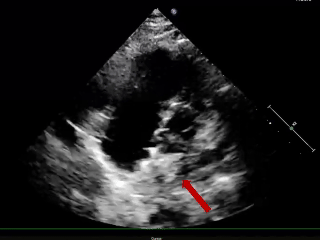

术后3个月随访

超声报告:(1)房间隔封堵器位置正常,各瓣叶形态活动未见异常,右心比例稍大,左房室腔不大,心包腔内未见液性暗区; (2)多普勒检查:房水平未见残余分流;心功能:室壁运动协调,未见节段性异常;(3)先天性心脏病房间隔缺损封堵术后未见残余分流。